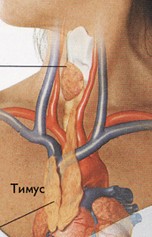

Фотографии вилочковой железы тимуса: структура и функции